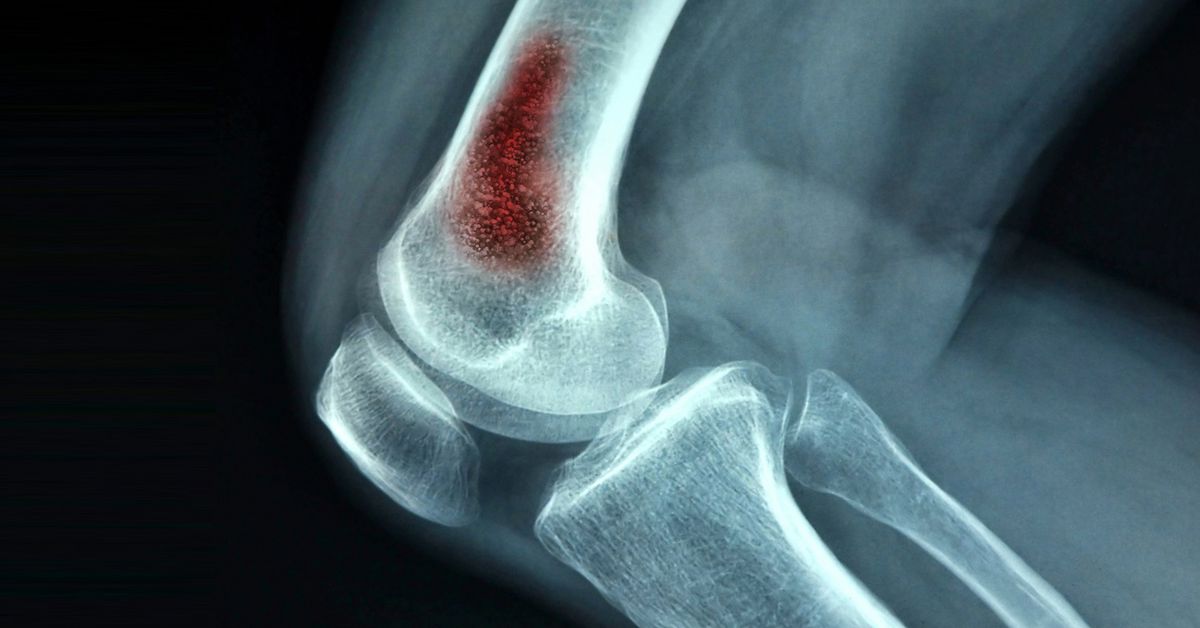

Osteomiyelit, bakterilerin veya nadiren mantarların kemiğe yerleşmesiyle oluşur. Bu durum, kemiğin iltihaplanmasına neden olan bir enfeksiyon türüdür. Genellikle açık yaralar, ameliyat sonrası komplikasyonlar sonucu gelişebilir. Vücutta bulunan başka bir enfeksiyonun kana karışması da bu duruma yol açabilir. Kemik enfeksiyonu tedavisi, enfeksiyonun şiddetine ve süresine göre planlanır. Hastanın genel sağlık durumu da tedavi sürecinde önemli bir rol oynar.

Kemik enfeksiyonu tedavisi, kemiğe yerleşen enfeksiyonların ortadan kalkmasını sağlar. Bu tedavi, enfeksiyonun yayılmasını önlemek, kemiğin yapısını korumak ve hastanın genel sağlığını desteklemek için uygulanır. Özellikle bazı durumlarda hızlı müdahale kritik bir önem taşır.

İlk ve en yaygın yöntem antibiyotik tedavisidir. Enfeksiyona neden olan bakterinin türüne göre uygun antibiyotik seçilir. Tedavi genellikle damar yoluyla uygulanır ve birkaç hafta sürebilir. Bazı vakalarda ağız yoluyla antibiyotik tedavisi de destekleyici olarak kullanılabilir. Antibiyotik tedavisi, enfeksiyonun ilerlemesini durdurur. kemiğin iyileşmesini sağlamak açısından kritik bir adımdır.

Bazı durumlarda kemik enfeksiyonu tedavisi cerrahi müdahale gerektirebilir. Enfekte bölgenin temizlenmesi, ölü dokuların çıkarılması veya iltihabın boşaltılması cerrahi yöntemle yapılır. Cerrahi tedavi, özellikle enfeksiyonun ilerlediği durumlarda önem kazanır. Ayrıca kemik dokusunun zarar gördüğü ve enfeksiyonun kronikleştiği vakalarda da uygulanır.

Tedavide en etkili yaklaşım genellikle antibiyotik tedavisidir. Cerrahi tedavi ile kombinasyon halinde uygulandığında başarı oranı artar. Tedavi süreci, erken tanı ve düzenli doktor kontrolleri ile desteklendiğinde enfeksiyon kontrol altına alınır. Bu sayede kemik sağlığı korunabilir. Tedavi yöntemlerinin doğru seçimi, hastanın yaşı, sağlık durumu ve enfeksiyonun yaygınlığına göre belirlenir.

Düzenli doktor kontrolleri, iyileşme sürecinin takip edilmesini sağlar. Röntgen veya MR gibi görüntüleme yöntemleriyle kemiğin durumu kontrol edilir. Ayrıca enfeksiyonun tekrarlayıp tekrarlamadığı da değerlendirilir. Ayrıca bağışıklık sisteminin güçlendirilmesi ve yeterli beslenme iyileşmeyi destekler. Sigara veya alkol gibi risk faktörlerinden uzak durmak da sürece katkı sağlar.